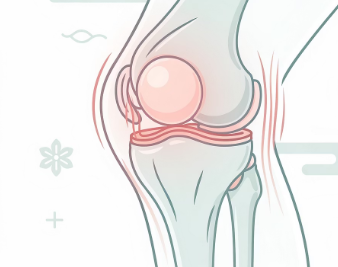

증상이 심해지는 상황과 특징

오래 서 있거나 많이 걸은 뒤

계단을 오르내릴 때

쪼그려 앉았다 일어날 때

무릎을 굽힌 상태로 오래 있을 때

이런 상황에서 붓기와 통증이 더 심해질 수 있습니다.